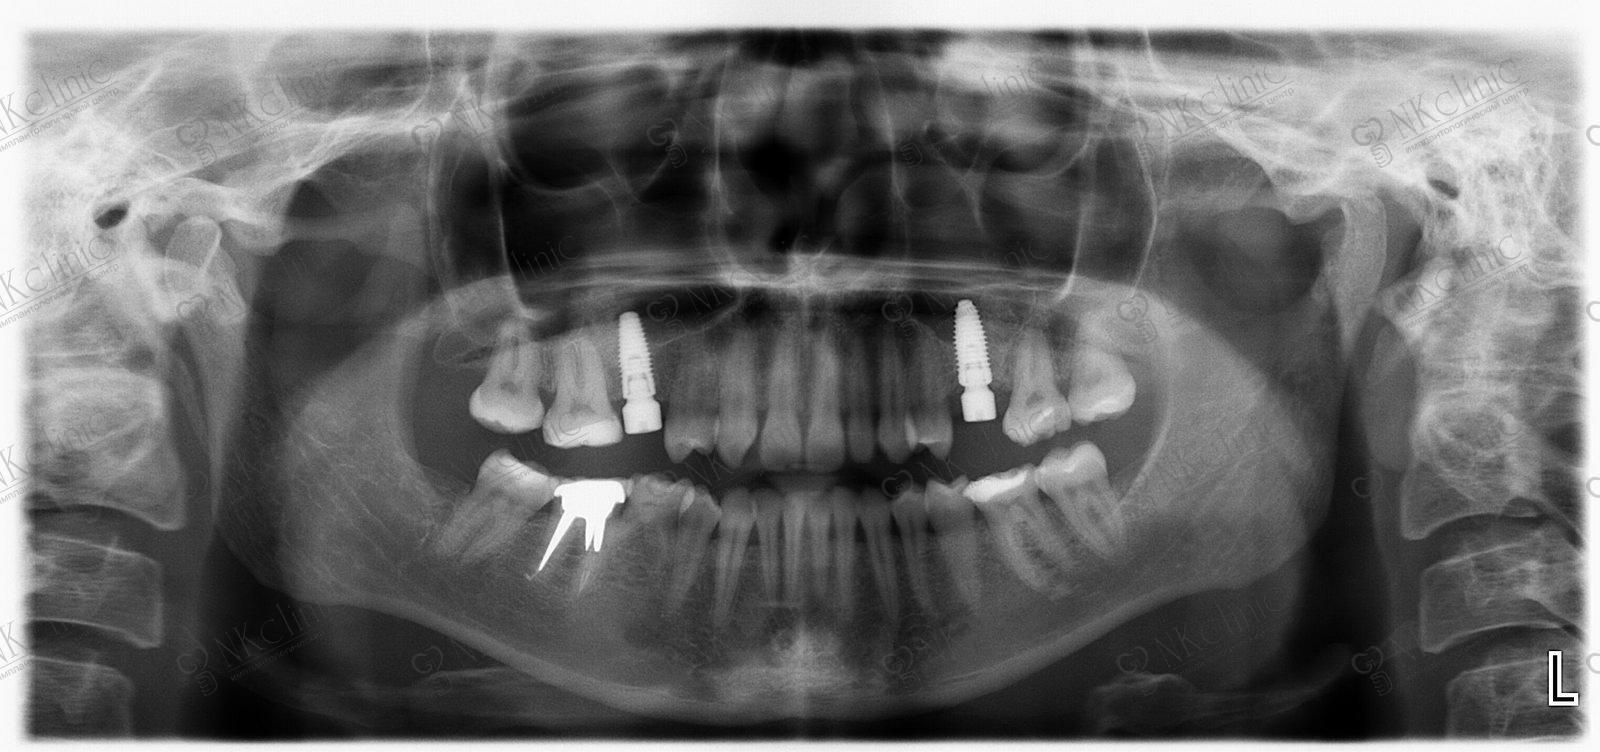

Технологические достижения: Planmeca и ОПТГ